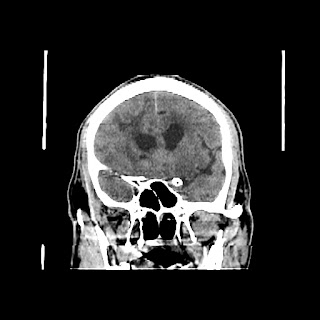

A 60 years old man with seizure since 12 years

Plan CT scan was done on 22 march 2016